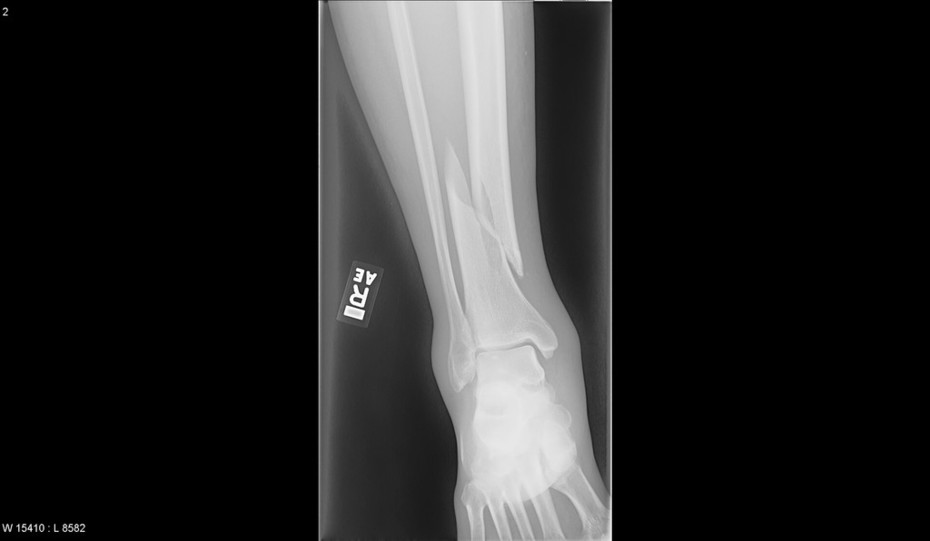

Tibial Shaft Fractures Trauma Orthobullets Sports Fracture Of Tibia Tibia plateau fractures most commonly occur from motor. Here we explain the various types and causes, as well as treatment and rehabilitation. Tibial plateau fractures occur by three main mechanisms. A tibial shaft fracture occurs along the length of the tibia (shinbone), below the knee and above the ankle. A tibia fracture in the lower leg is the most common. Sports Fracture Of Tibia.

Proximal Third Tibia Fracture Trauma Orthobullets Sports Fracture Of Tibia A tibial shaft fracture occurs along the length of the tibia (shinbone), below the knee and above the ankle. Tibia plateau fractures most commonly occur from motor. Tibial plateau fractures occur by three main mechanisms. A break in the shinbone just below the knee is called a proximal tibia fracture. A tibia fracture in the lower leg is the most. Sports Fracture Of Tibia.